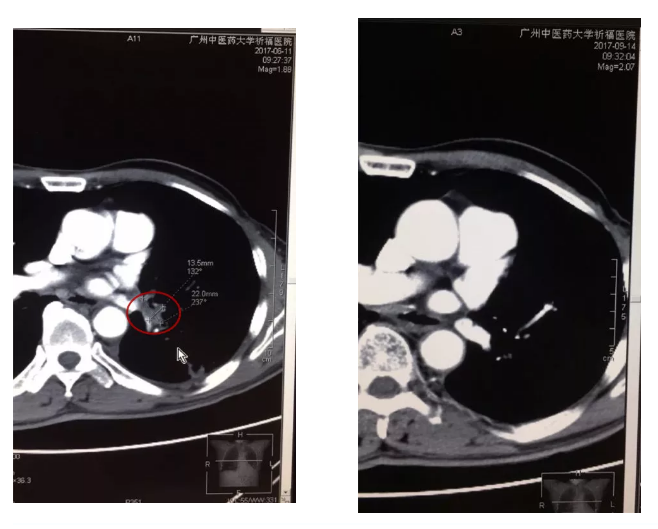

射频深部热疗的原理是利用射频电磁场作用于深部组织,利用热效应选择性破坏、杀伤病变细胞达到治疗目的,其特点是纳米范围的能量释放,其释放的能量利用效率可提升3-4倍。区俊文团队发现,大剂量VitC与mEHT同时结合使用,能令体内VitC峰值浓度显著增加[2],高浓度VitC以其氧化形式脱氢抗坏血酸(DHA)进入细胞后消耗大量还原型谷胱甘肽(GSH)和还原型烟酰胺腺嘌呤二核苷酸磷酸(NADPH),令癌细胞内活性氧簇(ROS)增加,进而引发DNA 损伤和断裂,泛素化蛋白酶体的活化,最终导致癌细胞凋亡。该研究发现这两个配角的组合,能够显著改善晚期NSCLC生活质量,延长生存期,还有部分病例肿瘤病灶显著缩小(图4),生存时间超过5年[1]。而且,从分组来看,上述治疗方法对于腺癌和鳞癌的患者,EGFR(+)与EGFR(-)的患者相比,没有统计学差异,这些发现提示,上述治疗方法对于不同病理类型的晚期肺癌患者疗效是相当的。这无疑对于晚期患者来说,多了一个治疗方案的选择,是一个福音。

图4   左图:治疗前:肺门的肿大淋巴结(红色圈内);右图:治疗后,肿大的淋巴结消失